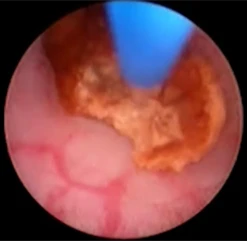

Через мочеиспускательный канал, в полость мочевого пузыря, вводится уретеропиелоскоп. Все манипуляции эндоскопическим инструментом, а особенно поступательное его продвижение по мочевым путям, должны проводиться под контролем зрения с тонко выверенной силовой нагрузкой, в случае потери эндоскопической картины возможно только одно направление движения инструмента - из пациента.

Через рабочий канал уретеропиелоскопа проводится лазерное волокно. По оптическому каналу изображение от эндоскопа передается на монитор. Волокно вплотную подводится к камню и при нажатии на педаль подаётся лазерное излучение, вследствие которого происходит деструкция камня.

Добившись нужной дисперсности фрагментов камня, их элиминируют корзинкой, либо другими видами экстракторов (петли, щипцы). Производится эндоскопическая ревизия мочеточника. Подтверждается полное удаление фрагментов камня. Уретеропиелоскоп удаляется.